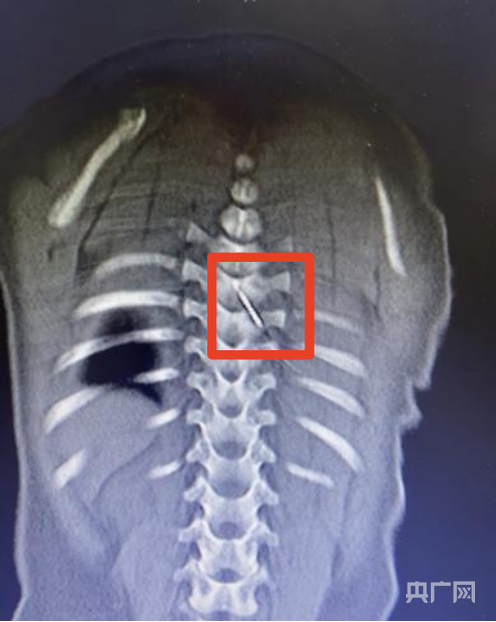

影像下,刺入男婴的缝衣针(央广网发 安徽省儿童医院供图)

据介绍,缝衣针裹在被子里,在男婴睡觉时扎进了他的后背,并随着身体移动不断深入,刺入脊柱内,紧贴脊髓的危险区域。

“这是我见过最危险的异物损伤之一。” 安徽省儿童医院儿童骨科主任医师张亚鹏说,“针的位置极其刁钻,周围密布重要血管和神经,就像在布满电线的墙壁里取一根针。”

当日凌晨2时,儿童骨科、麻醉与围术期医学科、儿童重症医学科、影像科多学科专家组成的抢救团队通过三维CT影像,精确还原了针的走行路径和周围解剖结构。在高倍显微镜下,医生们于脊髓腔外侧安全区域,精准、完整地取出缝衣针。